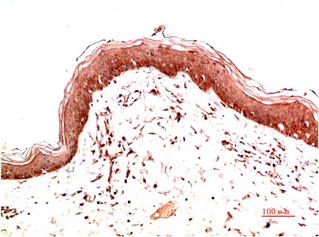

Immunohistochemical analysis of paraffin-embedded Human Skin Carcinoma Tissue using Collagen I Mouse mAb diluted at 1:200.